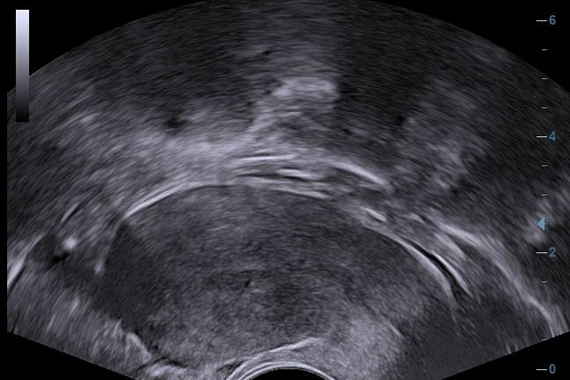

Клинические изображения

- V11-3 - Микроконвексный внутриполостной датчик для гинекологии, акушерства, урологии

- V10-4B - Микроконвексный внутриполостной датчик с эргономичной изогнутой рукояткой для гинекологии, акушерства, урологии